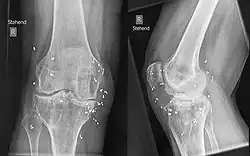

Bei der klassischen Goldstückchenimplantation werden kleine zylindrische Segmente (etwa 1 bis 3 Millimeter lang) aus 24-karätigem Golddraht von 1 Millimeter Durchmesser gelenknah implantiert. Die Segmente werden beim Menschen in lokaler Betäubung, beim Tier in Sedation mittels einer Hohlnadel rund um das Gelenk eingebracht. Die Stücke liegen außen an der Gelenkkapsel, nicht im Gelenk. Die Anzahl schwankt je nach Gelenk zwischen 10 und 50 Stück.

Die Goldimplantation wird bei Menschen als Therapie bei degenerativen, traumatischen oder entzündlichen Gelenkveränderungen eingesetzt, die mit Schmerzen einhergehen. Sie findet Anwendung bei Arthrose der Knie, der Hüften, der Hals-, Brust- und Lendenwirbelsäule, der Schultergelenke, der Fuß- und Handgelenke einschließlich der Fingergelenke. Hauptziele sind die Schmerzreduktion durch Eindämmung der Entzündung und eine Zunahme der Beweglichkeit. Der Eingriff erfolgt am Menschen unter Lokalanästhesie.

In der Tiermedizin wird die Goldimplantation zum Beispiel angewandt bei Hüftdysplasien, Osteochondrosis, Osteochondrosis dissecans der Schulter, Arthritis des Ellenbogens und des Knies, Spondylose des Rückens, Ankylosen, Cauda-equina-Kompressionssyndrom, Wobbler-Syndrom und epileptischen Anfällen von Hunden. Vor der Behandlung werden neben dem Einsatz von Röntgentechnik üblicherweise eine Gangbildanalyse und Triggerpunktuntersuchung durchgeführt. Eingenommene schmerzarme Schonhaltungen verändern den Bewegungsablauf und geben zusammen mit Bewegungsschwächen (Lahmheiten) Aufschluss über den Problembereich.